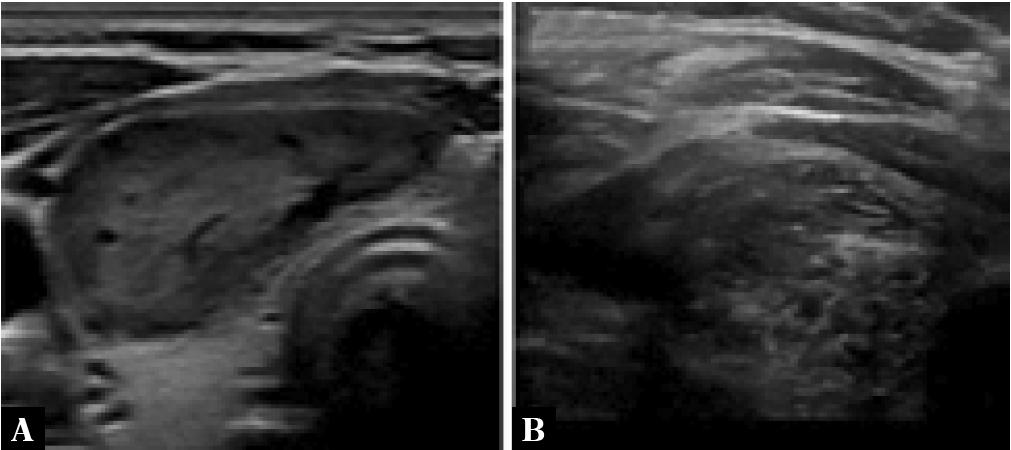

Greyscale sonographic images of: A. spongiform nodule and B. a mixed cystic and solid nodule. Compared to (B), the cystic spaces are smaller and more evenly distributed (A)

By definition, a spongiform nodule is one that is composed of >50% of small cystic spaces that are evenly distributed throughout the nodule – this appearance resembles a sponge (Fig. 7)(3). Intermediate nodules that do not meet this criterion but show a <80% solid volume should be described as being of mixed cystic and solid composition. When echogenic foci are found in a spongi-form nodule, these are not considered as PEF and should be ignored(4).

Fig. 7